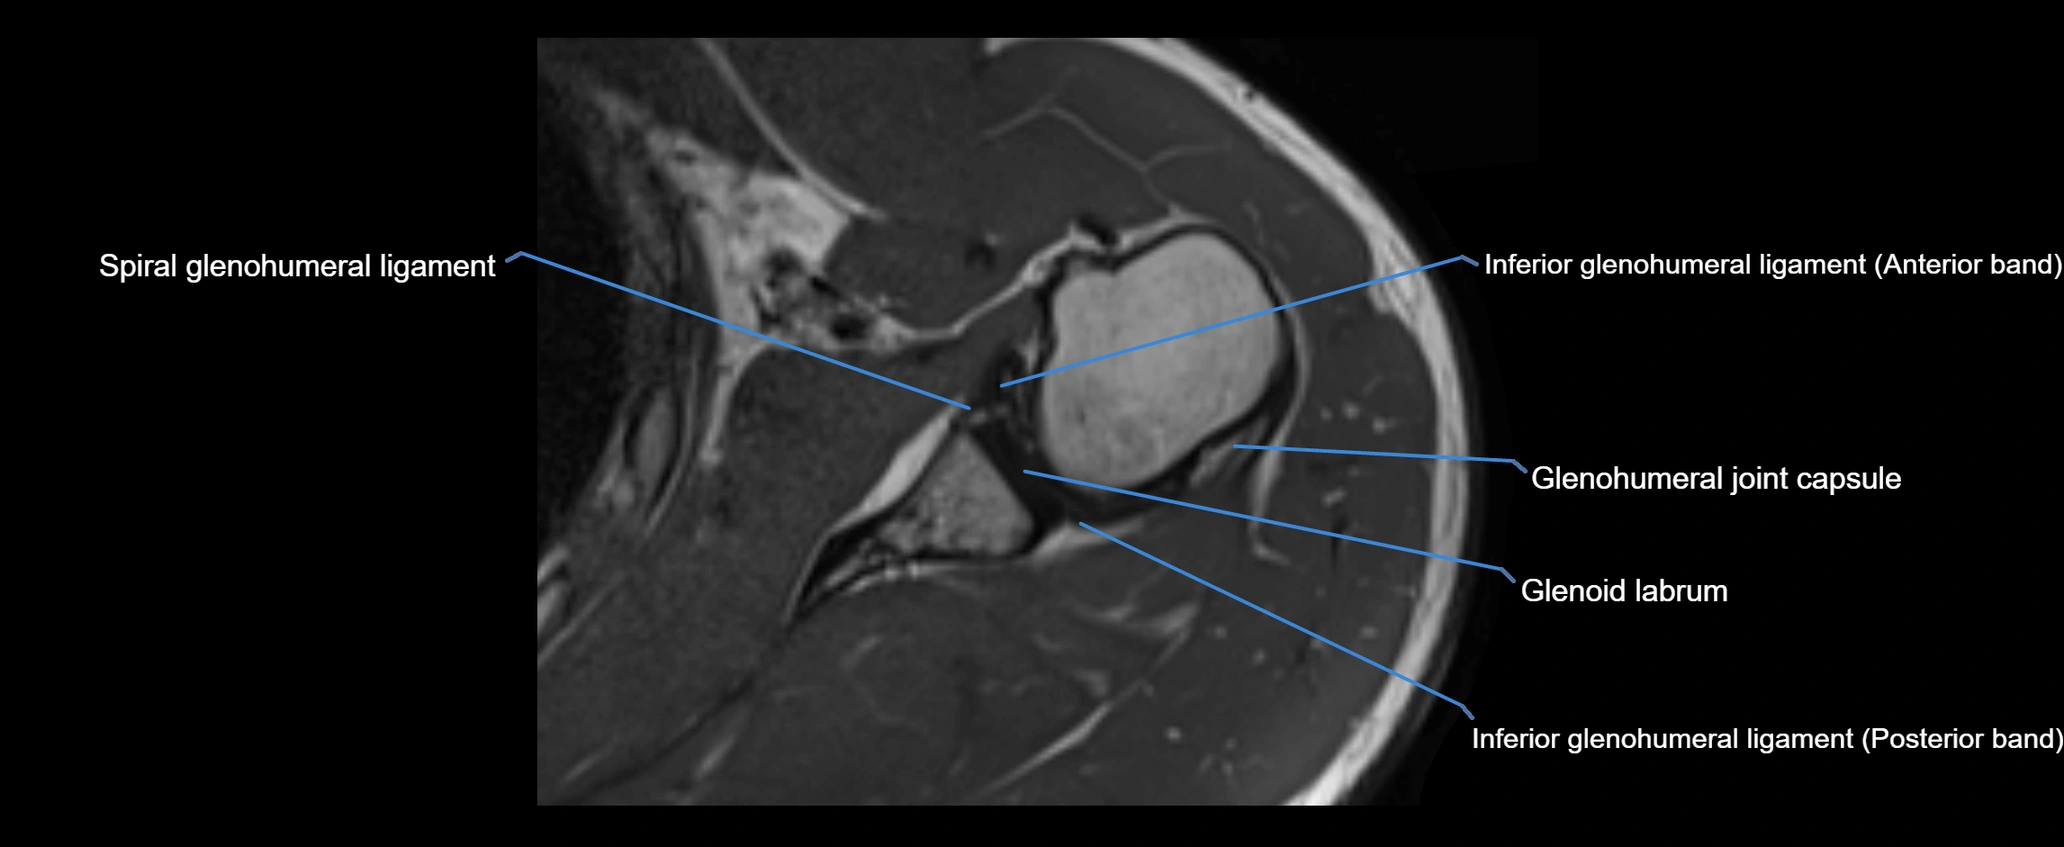

MRI images

image